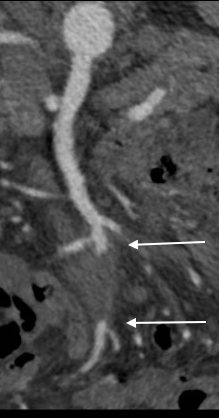

The patient is a middle aged man with risk factors of NIDDM and prior history of DVT who developed severe mid-abdominal pain at 5pm. He came to the ED at around 11pm and had a general surgery consultation who ordered a CT Angiogram showing SMA occlusion (pictured below).

Heparin was started, and at 11:30, vascular surgery was consulted. The patient had a soft, doughy texture to his abdomen, but great pain with palpation -classic pain out of proportion to the exam. Determining the patient to have acute mesenteric ischemia from a thromboembolism, I took the patient to our hybrid angiographic OR suite with the plan for arteriography, possible open thrombectomy, and exploratory laparotomy.

Arteriography from femoral access showed an occlusion of the SMA beyond the middle colic artery, a typical pattern for an embolism that occurs when embolism lodges distally and propogates proximally (image below).